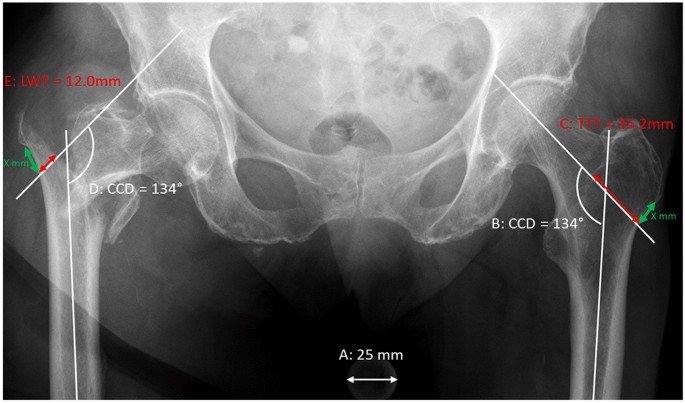

*Relative lateral wall thickness is an improved predictor for *